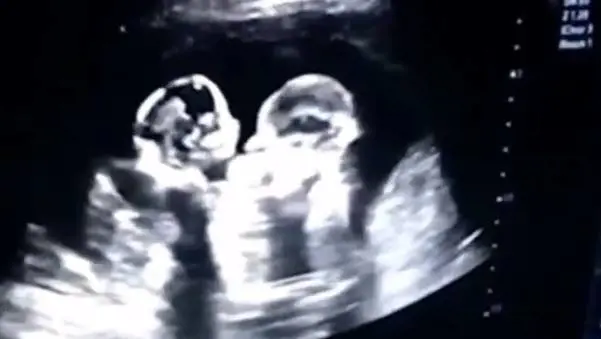

Diventate star del web e dei social ancora prima di nascere. È successo a due gemelline cinesi, nella città dello Yinchuan, quando alla fine dello scorso anno il padre Tao ha caricato in internet il video dell'ecografia di controllo prenatale.

Il filmato, reso pubblico sull'app per video brevi Douyin, è diventato virale in breve tempo, collezionando mi piace e condivisioni a pioggia. Nelle immagini registrate dall'uomo si vedono le bimbe che sembrano quasi combattere tra di loro, in un gioco di lotta.

Le bimbe, nate in salute, hanno ricevuto i soprannomi di "Ciliegia" e Fragola", come i frutti preferiti dalla madre durante la gravidanza. Ma le gemelline lottatrici non si sfidano solo a suon di "colpi": il Daily Mail, infatti, riferisce che il padre ha raccontato di aver visto le figlie abbracciarsi, durante un altro controllo, mentre la moglie stava facendo un test sul liquido amniotico. "Siamo stati così toccati- ha detto il padre- Le bambine erano così piccole e sapevano come prendersi cura l'una dell'altra. Credo che vivranno l'un l'altro in armonia quando cresceranno ".

Sembra che le gemelline condividessero lo stesso sacco amniotico e la stessa placenta: si tratta dei gemelli Mo-Mo, monoamniotici e monocoriali. Si tratta di una delle gravidanze più ad alto rischio, con una sopravvivenza incerta, secondo i dati riportati dal Daily Mail.